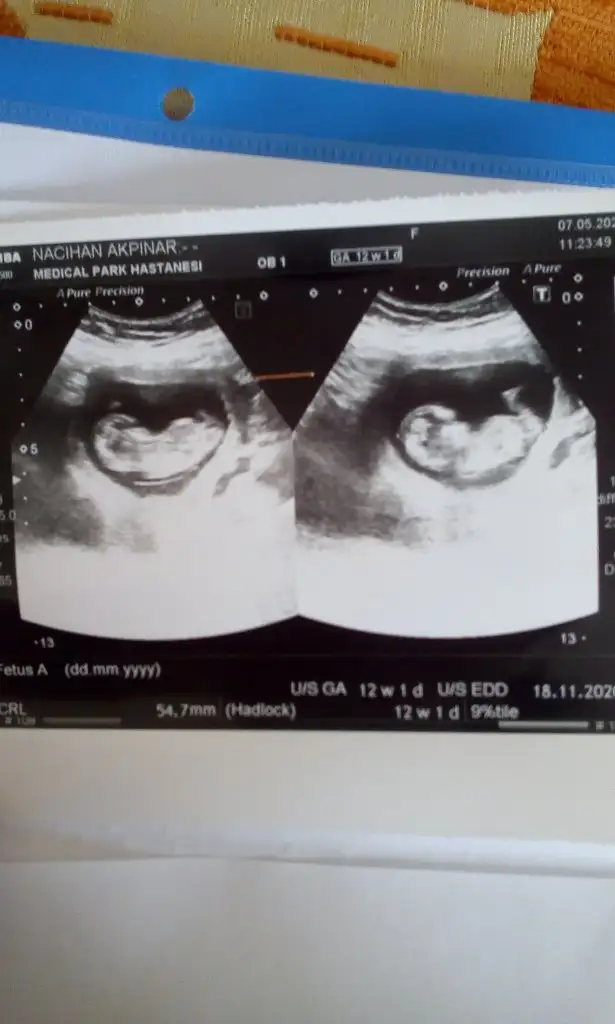

MrB hanimlar 12+1 günlük cinsiyeti ne olabilir yardımcı olursanız sevinirim

Eklentiler

• IMG-20200507-WA0023.webp

21,9 KB · Görüntüleme: 83

• IMG-20200507-WA0018.webp

17,8 KB · Görüntüleme: 84